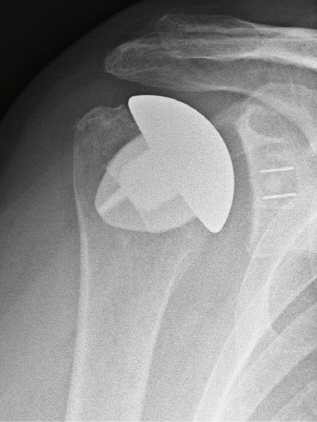

Wann immer möglich wird ein sog. Humeruskopfersatz verwendet. Diese schaftfreie Schulterendoprothese erlaubt einen sehr knochensparenden Ersatz des Schultergelenkes und ermöglicht auch einen Austausch der Gelenkpfanne, falls diese sich im Laufe der Jahre auch abnutzt. Vorraussetzung für den alleinigen Ersatz der Kopfes ist eine ausreichend gute Knorpelschicht auf der Pfanne. Sollte irgendwann einmal eine Wechseloperation notwendig sein, bleiben durch die knochensparende Implantation alle Möglichkeiten für einen Wechsel der Prothese erhalten. Das Fallbeispiel zeigt eine Nekrose (Abgestorbener Knochen) eines großen Teils des Oberarmkopfes. Das Bild mit eingebrachter Kopf-Prothese den Zustand 5 Jahre nach der Operation.